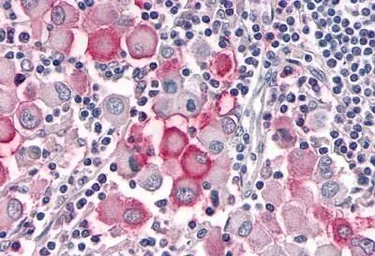

OR10R2 antibody

Cat. No. GTX71527

ApplicationsIHC-P

ReactivityHuman, Rabbit, Bovine, Monkey